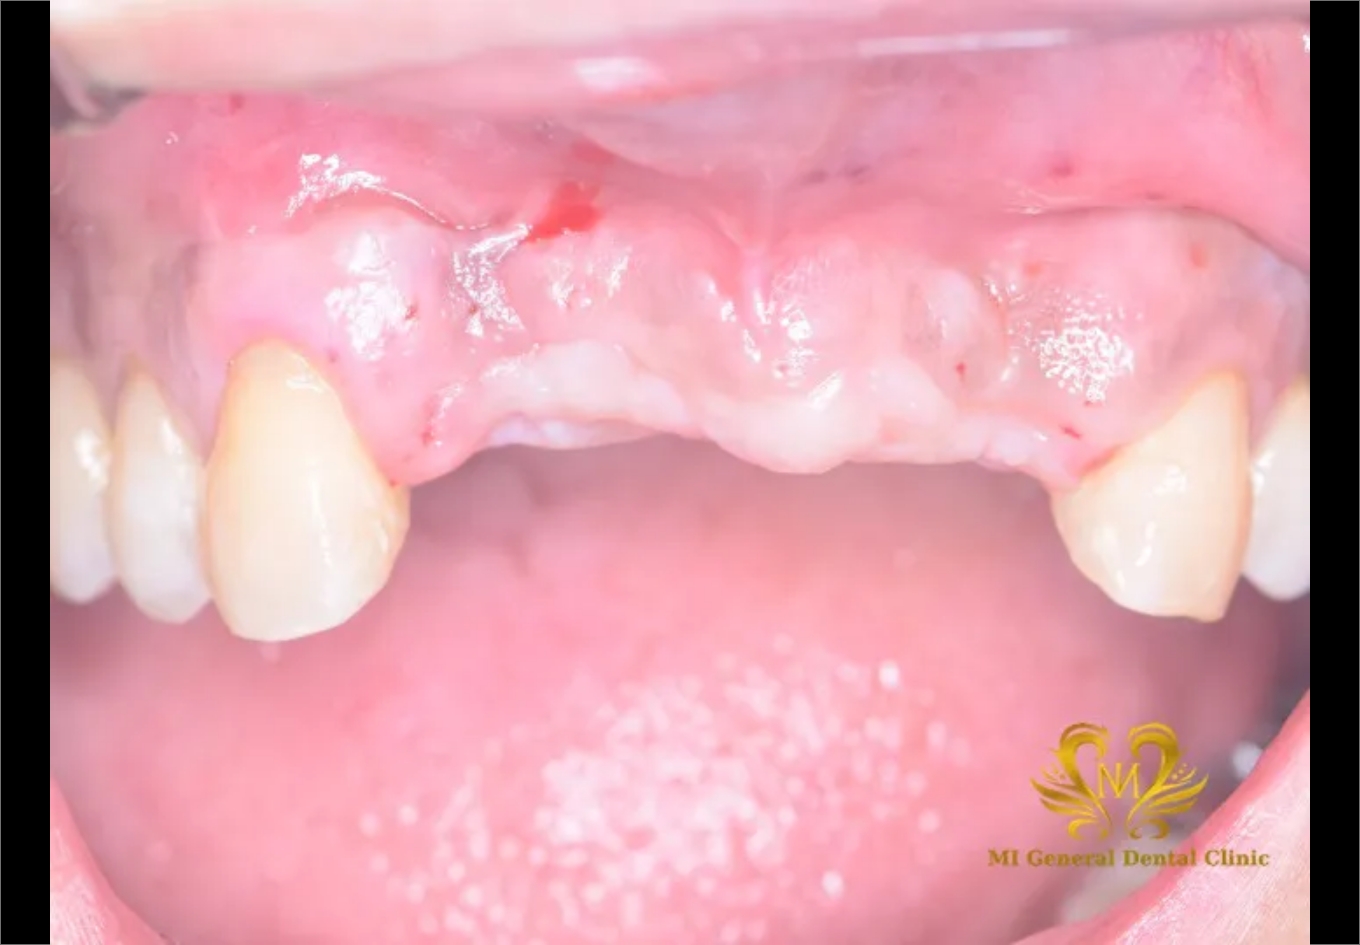

治療前

前歯4本を残念ながら失った患者さんです。

審美障害と前歯が噛めないという主訴にて来院。